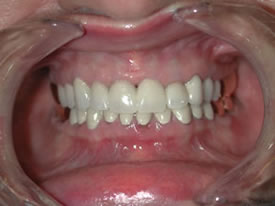

| Notice how the reconstruction affects

not only the occlusion (the way her teeth fit together), but

also the way her smile is expressed throughout her lower face! |

After